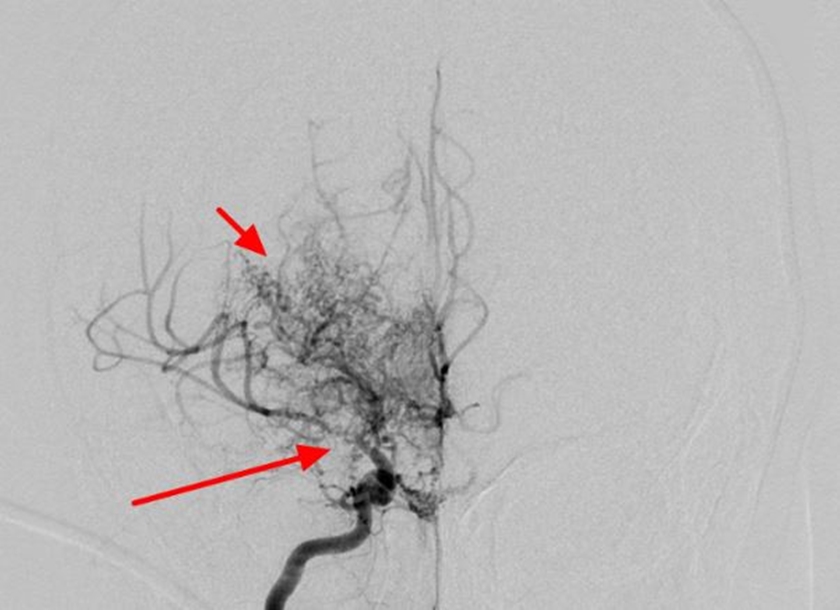

모야모야병은 뇌질환입니다. 뇌혈관이 좁아지거나 막히게 되어서 허혈이 진행하게 되면 뇌기저부에 이상혈관이 만들어 지게 되는데 이상혈관의 모양이 연기가 피어오르는 모양처럼 보인다고 합니다.